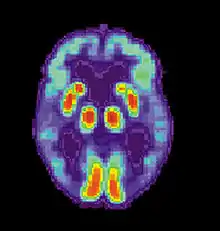

PET Normal brain

Normal brain

PET Alzheimer patient

Alzheimer patient

PET scan of normal (left) and Alzheimer's patient brain (right)

Current Research indicates that procedural memory problems in Alzheimer's may be caused by changes in enzyme activity in memory-integrating brain regions such as the hippocampus. The specific enzyme linked to these changes is called acetylcholinesterase (AchE) which may be affected by a genetic predisposition in an immune-system brain receptor called the histamine H1 receptor. The same current scientific information also looks at how dopamine, serotonin and acetylcholine neurotransmitter levels vary in the cerebellum of patients that have this disease. Modern findings advance the idea that the histamine system may be responsible for the cognitive deficits found in Alzheimer's and for the potential procedural memory problems that may develop as a result of the psychopathology.[61]